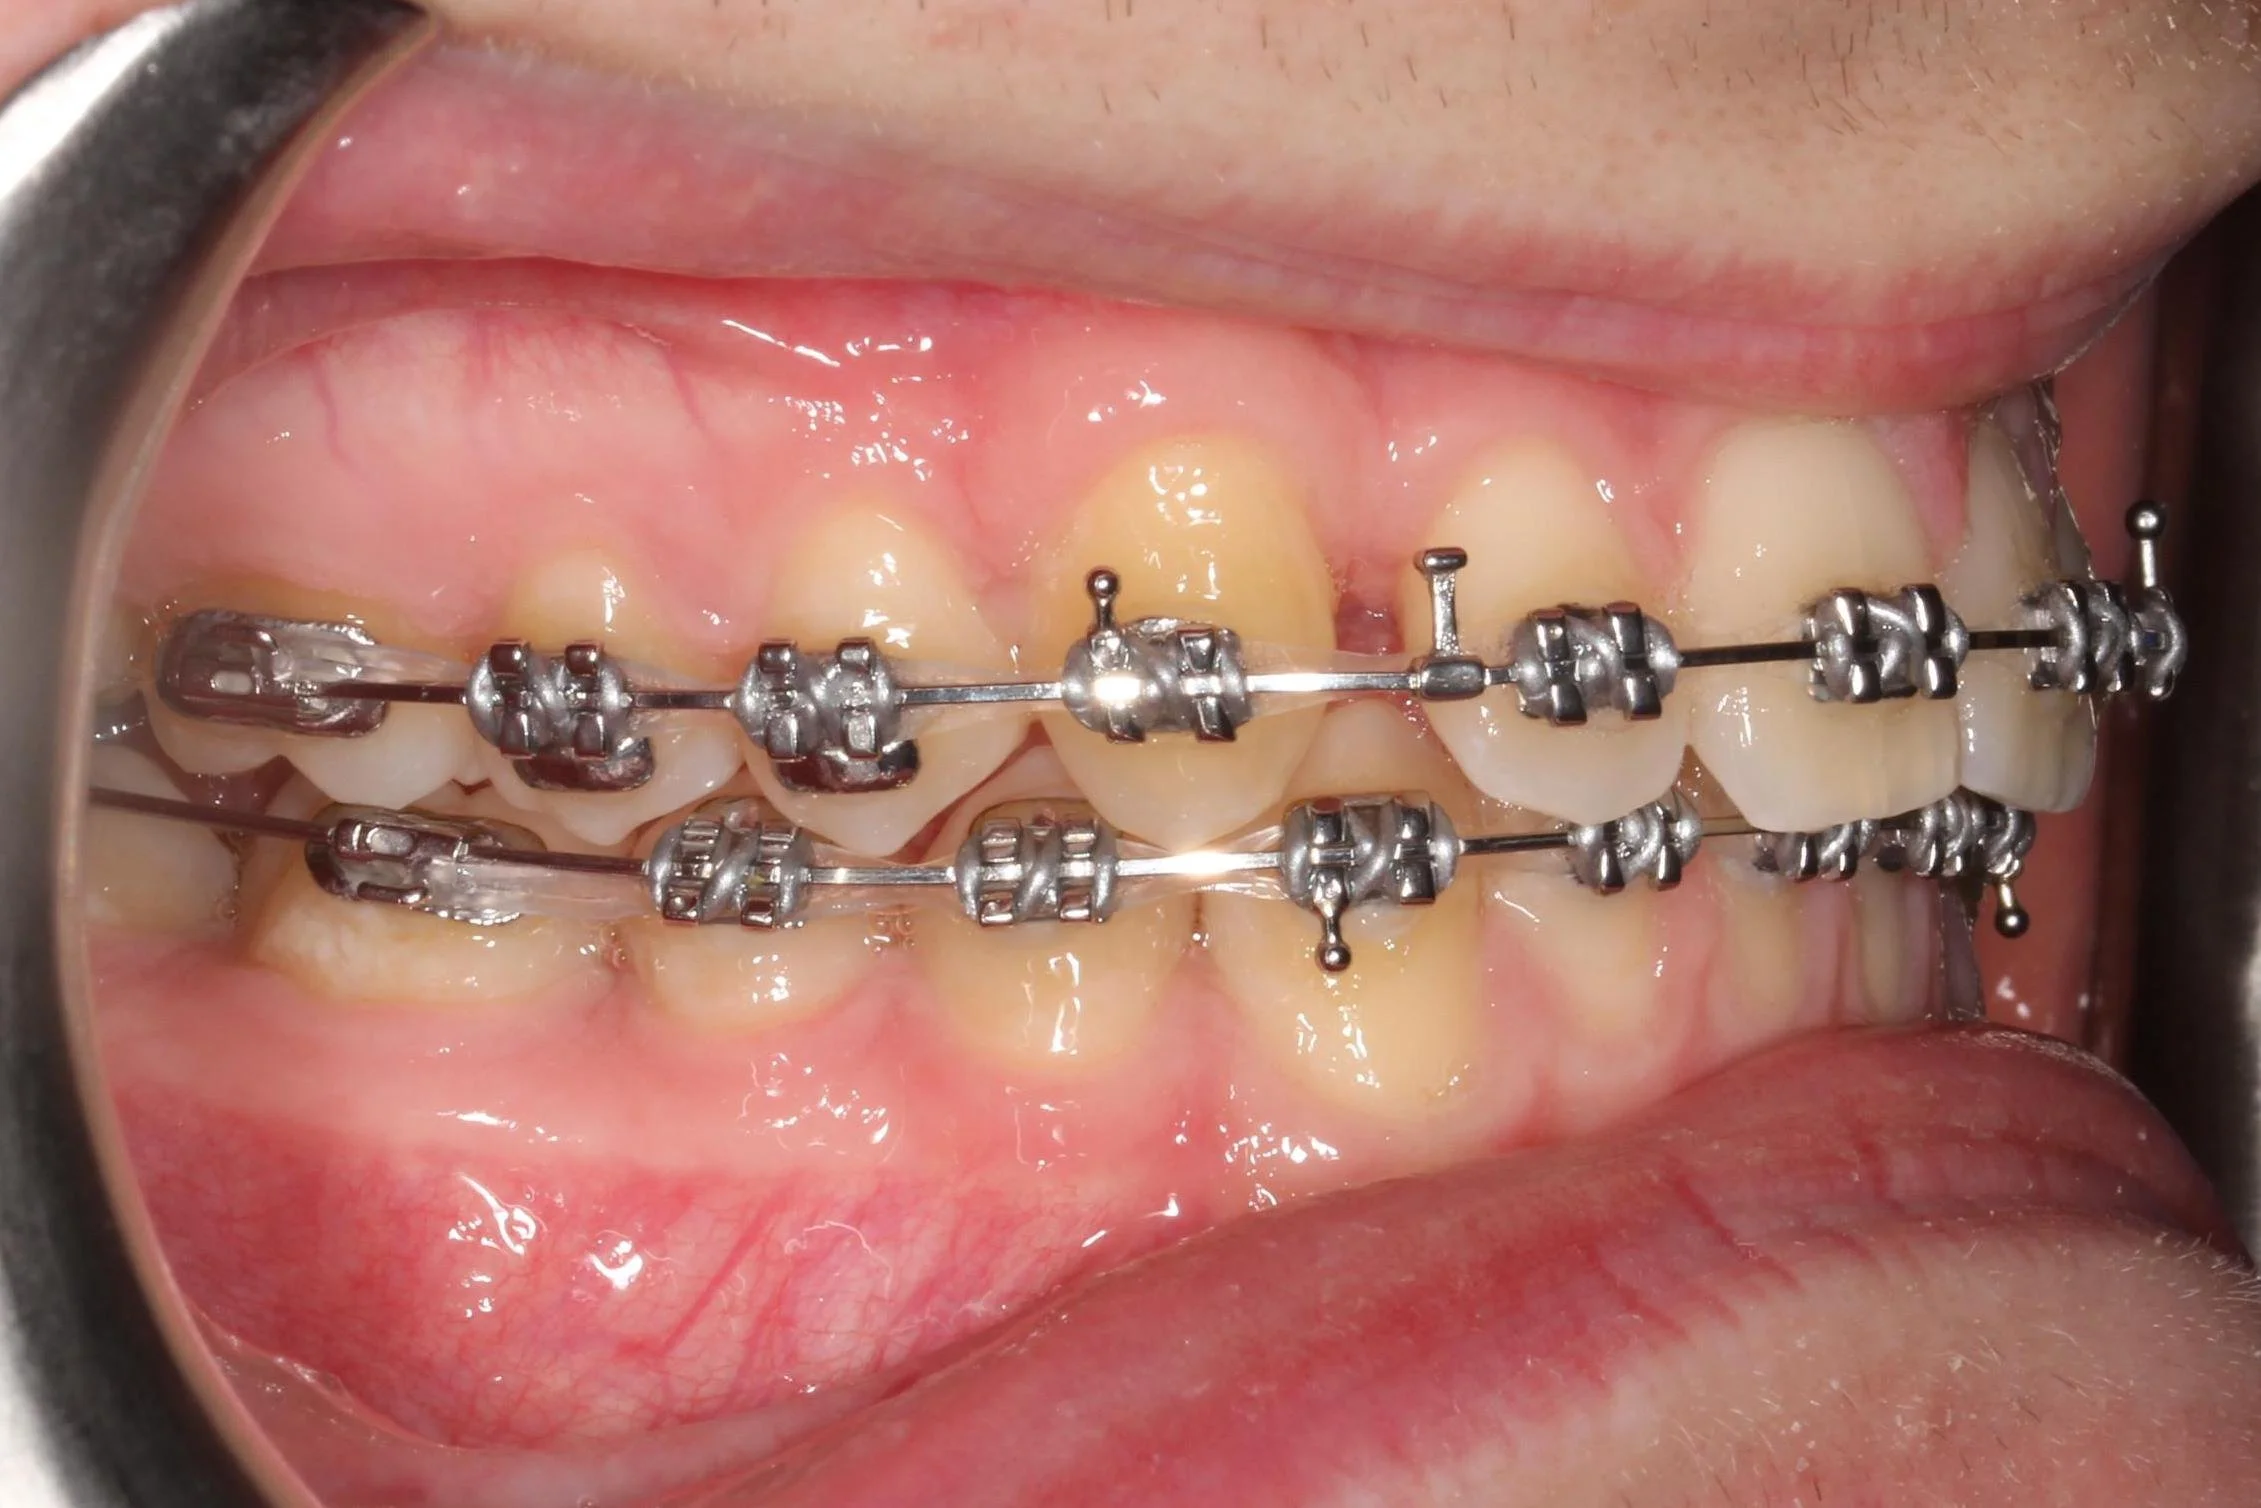

alt="metal fixed braces"

Upper & lower metallic fixed braces

Upper metallic fixed brace in place with general spacing following expansion

Upper metallic fixed brace in place with space in canine positions